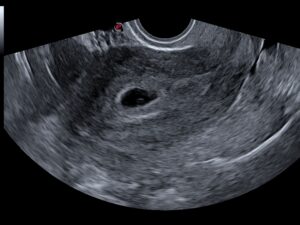

Early Pregnancy Ultrasound - Up till 10 weeks

This scan determines a live pregnancy, location of the pregnancy (in case it is out of the uterus – an ectopic pregnancy), and can pick up multiple pregnancies.